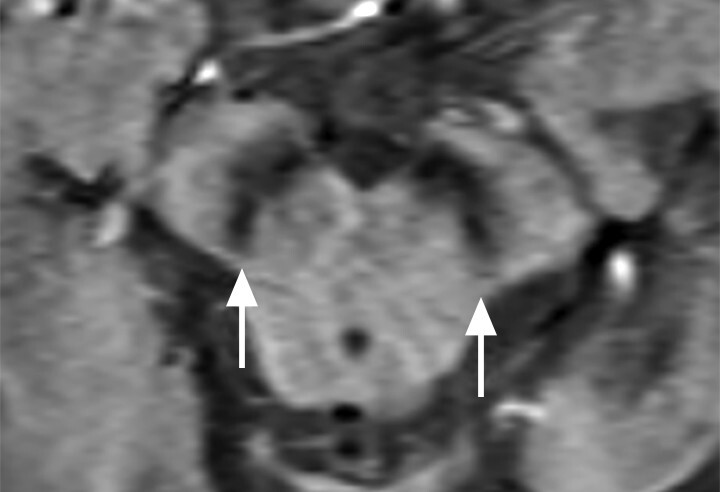

- Der Nachweis der Degeneration des dopaminproduzierenden Nigrosoms 1 innerhalb der Substantia nigra und des damit verbundenen Verlusts des Schwalbenschwanzzeichens (Swallow Tail Sign; Abb. 69.2) zeigt keinen eindeutigen Mehrwert in Bezug auf Diagnose und Differenzialdiagnose von Parkinson-Syndromen. Die Beurteilung des Schwalbenschwanzzeichens ist nämlich deutlich scanner- und befunderabhängig und wird in bis zu 50% der Fälle auch bei Patientinnen und Patienten mit frontotemporaler Demenz und Alzheimer-Demenz als anomal eingestuft [12].

Abb. 69.2 Parkinson-Syndrome.

a Schwalbenschwanzzeichen beidseits als Ausdruck eines unauffälligen dopaminproduzierenden Nigrosoms 1 (Pfeile).

b Beim idiopathischen Parkinson-Syndrom, aber auch bei anderen neurodegenerativen Erkrankungen, ist das Schwalbenschwanzzeichen (Swallow Tail Sign) in der SWI-MRT (Schichtdicke 2 mm) einseitig oder beidseitig nicht abgrenzbar (Pfeile).